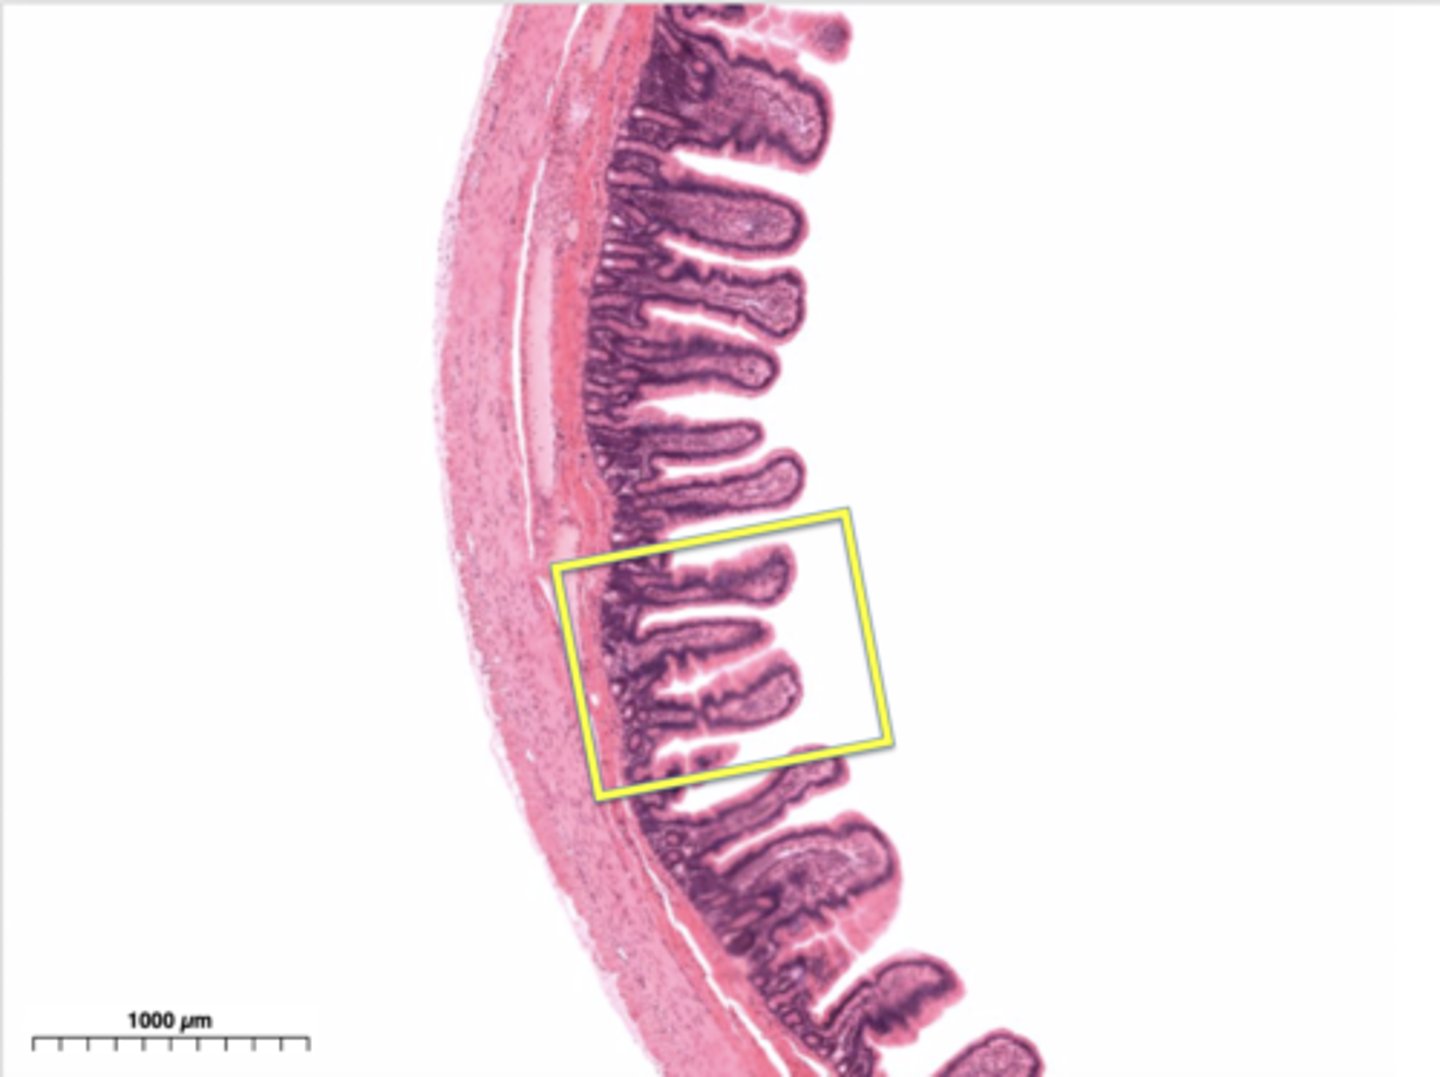

Which organ is this?

Esophagus